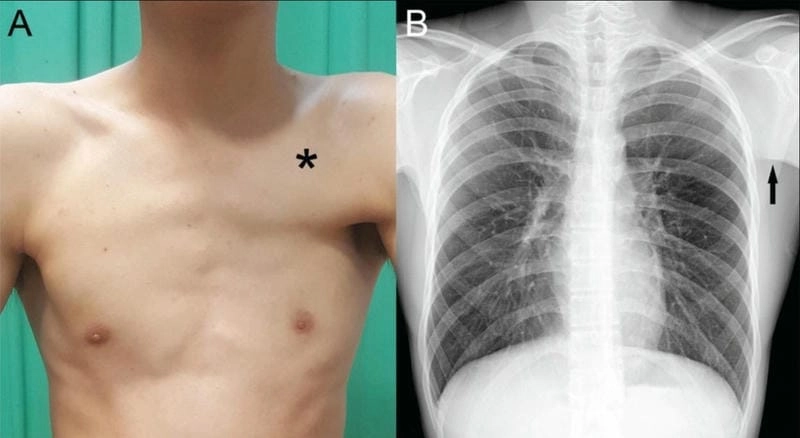

Hình ảnh bệnh còi xương là tư liệu quan trọng giúp phụ huynh sớm nhận biết dấu hiệu bất thường ở trẻ. Việc quan sát đúng hình ảnh giúp hiểu rõ biểu hiện bệnh lý, từ đó kịp thời phòng ngừa và điều trị hiệu quả ngay từ giai đoạn đầu.

Không thể tin nổi đây là sự thật – loạt hình ảnh bệnh còi xương chân thực dưới đây ghi lại những khoảnh khắc ám ảnh về sự tàn phá thầm lặng của căn bệnh này. Từ những khung xương cong vẹo, đầu to bất thường đến thân hình yếu ớt như chiếc lá khô, mỗi tấm ảnh là một câu chuyện đau lòng. Bộ sưu tập này không chỉ giúp bạn hình dung rõ hơn về hình ảnh bệnh còi xương, mà còn thức tỉnh sự quan tâm tới sức khỏe trẻ nhỏ – đối tượng dễ bị tổn thương nhất.

Việc nắm rõ hình ảnh bệnh còi xương giúp cha mẹ không chỉ nhận biết mà còn chủ động trong việc chăm sóc dinh dưỡng, phòng tránh nguy cơ cho trẻ. Cùng theo dõi hình ảnh điển hình để có biện pháp can thiệp hợp lý và đúng thời điểm.